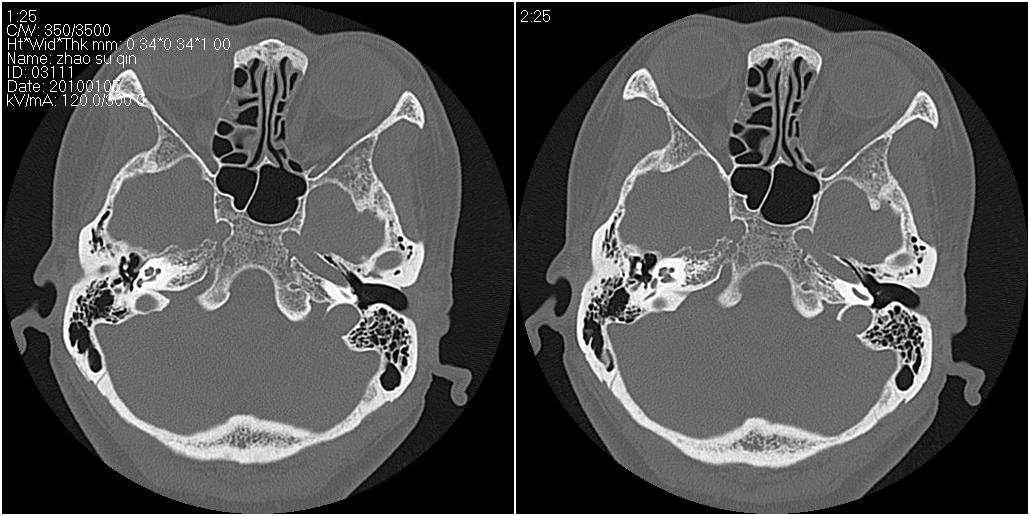

标题: CT24015:一个头部外伤患者进行鉴定,除了左侧筛板骨折,哪 [打印本页]

标题: CT24015:一个头部外伤患者进行鉴定,除了左侧筛板骨折,哪

看了几遍,其余未见明显骨折征。

1)左侧筛板骨折。2)双侧筛窦炎症(或积血)。

其余未见明显骨折征。